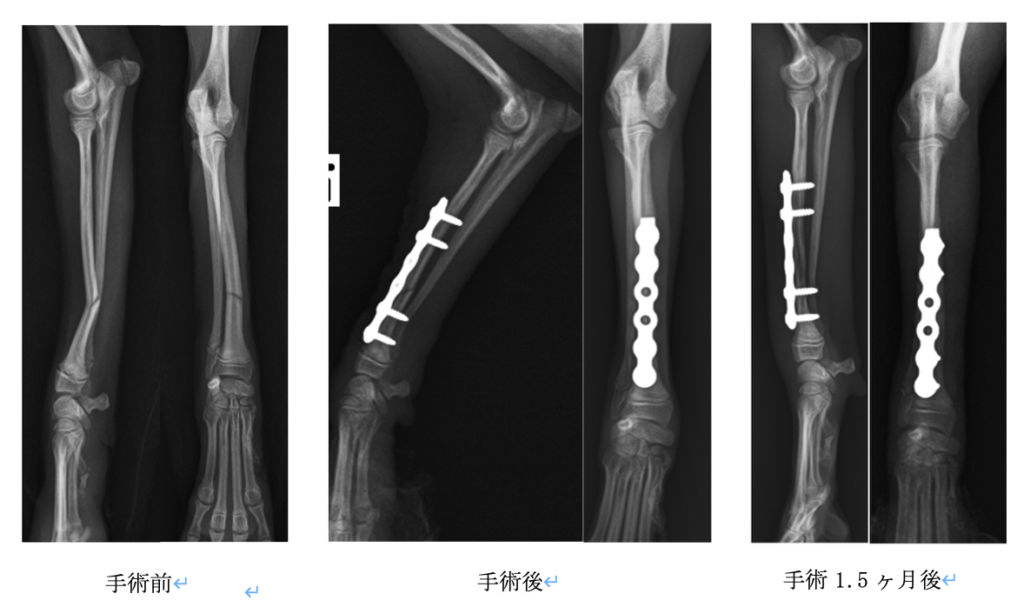

レントゲンを撮影すると橈骨に骨折を認めましたので、その日にプレートを用いた整復手術を実施し

ました。プレートはジョンソン・エンド・ジョンソン社のLCP1.5を使用しました。

術後1.5ヶ月で仮骨(治癒の過程でできる新しい骨組織)の形成を確認しました。その後は真ん中2本のスクリューを抜く手術を行います。間引きをすることで骨に体重がかかり骨の癒合が促されます。体重が1kgほどととても小さなわんちゃんなので、今後も慎重に経過を見ていく必要があります。